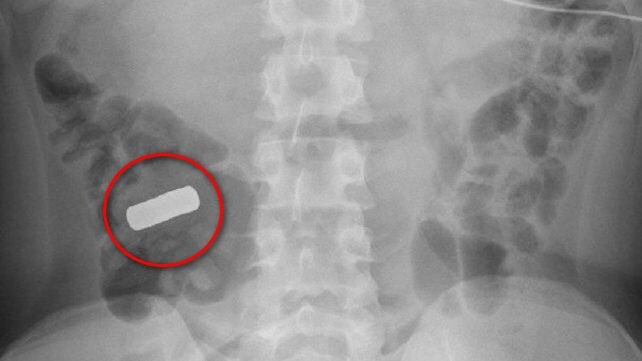

I magneti al neodimio sono composti da una lega con altri elementi (come boro e ferro) e sono rivestiti da antiossidanti alla stregua del nichel e dello zinco, che impediscono al materiale di ossidarsi e sfaldarsi, essendo il neodimio estremamente reattivo. I giochi basati su questo elemento sono venduti in set da decine di pezzi, principalmente composti da sfere, monete, bacchette, cubi, piastrine, cilindretti e altre forme, che possono essere organizzate per creare le strutture più disparate. Piacciono molto perché sono divertenti e alimentano la creatività. Ma purtroppo non sono innocui. Tutt'altro.

I magneti possono provocare lesioni orribili se ingoiati in serie, continuando a interagire all'interno del tratto digerente provocando lacerazioni o adesioni dei tessuti, perforazioni degli organi, avvelenamento, ostruzione intestinale e altre gravi condizioni che nei casi peggiori possono anche portare alla morte, come purtroppo accaduto a diversi piccoli. Ecco perché la raccomandazione è quella di tenere questi oggetti fuori dalla portata dei bambini. I dettagli della ricerca “Socioeconomic Disparities in Pediatric High-Powered Magnet Ingestion Epidemiology and Outcomes” saranno presentati il 22 ottobre presso la AAP National Conference & Exhibition del 2023 al via da oggi a Washington DC, negli Stati Uniti.